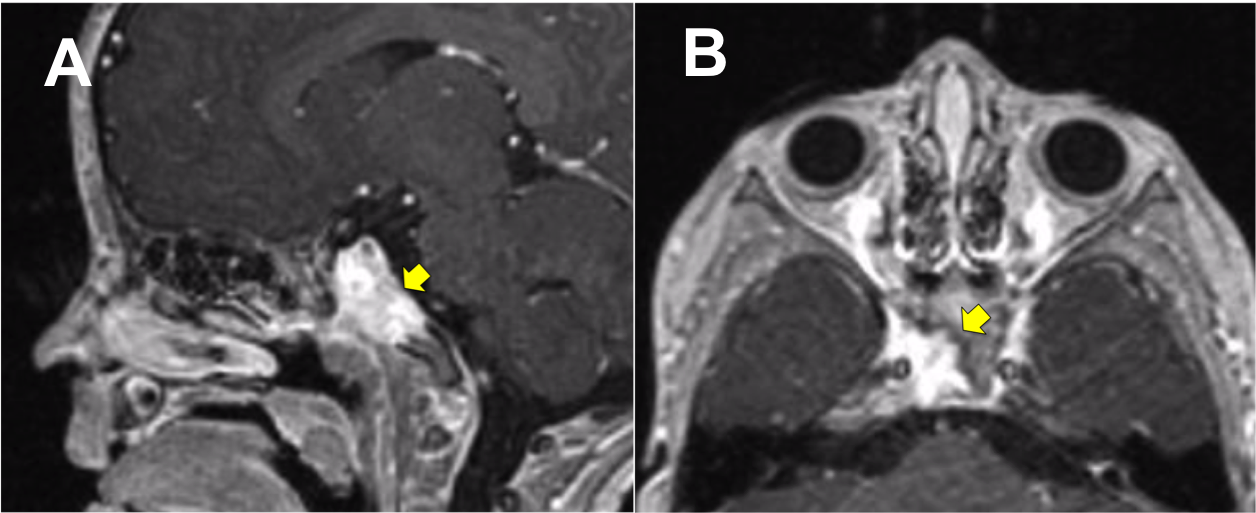

Introducción: La cirugía endoscópica endonasal se ha convertido en una herramienta fundamental para el manejo de patologías que comprometen la base de cráneo. En casos bien seleccionados, estas técnicas permiten resecciones quirúrgicas con una menor morbilidad sin comprometer los principios oncológicos de resección. Con el desarrollo de instrumental especializado, nuevas tecnologías y la experiencia de los cirujanos, la cirugía endoscópica endonasal se usa cada vez más en cirugía de base de cráneo en niños.

Resultados: Fueron intervenidos 8 pacientes entre los 2 y 14 años, con una edad promedio de nueve años y un seguimiento promedio de 16 meses. En el 75% se hizo una resección total del tumor. Un paciente requirió una reintervención y un paciente fue sometido a radiocirugía post-operatoria. 1 paciente falleció a pesar de múltiples intervenciones, quimioterapia y radioterapia.

Conclusión: La cirugía endoscópica endonasal para tumores de base de cráneo puede ser utilizada de forma segura en los pacientes pediátricos, es una técnica que en casos bien seleccionados pueden ofrecer excelentes resultados disminuyendo la morbilidad y complicaciones de las técnicas abiertas.